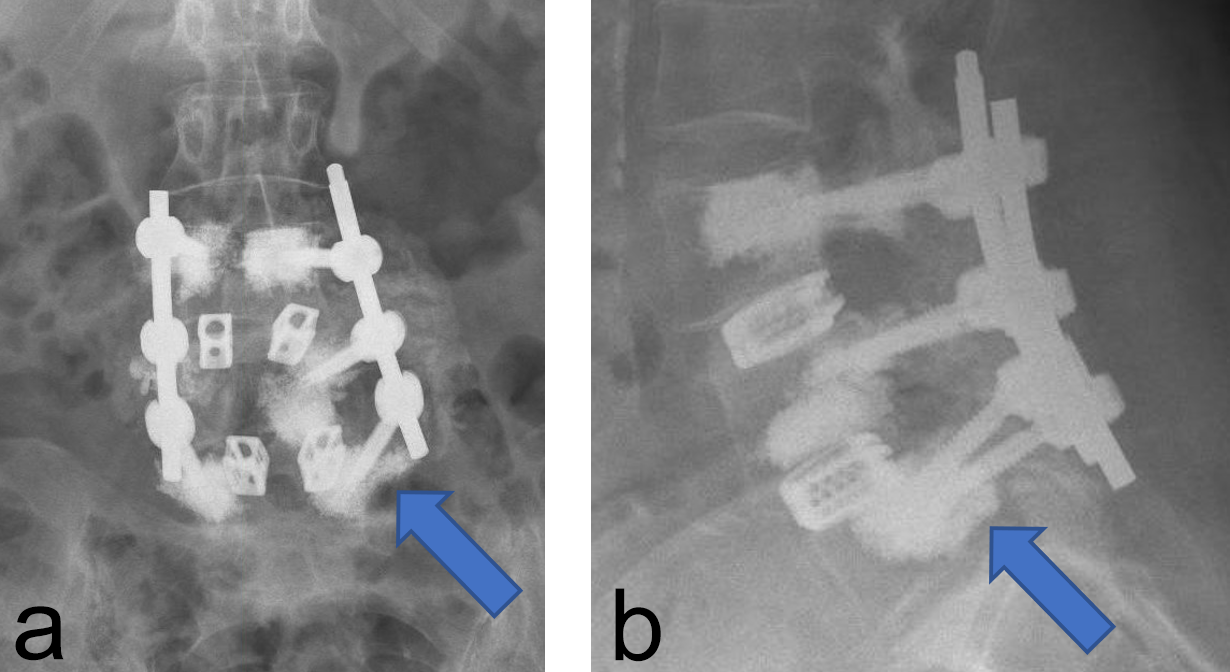

Instrumentation failure occurred in 7 (11.5%) of 61 patients. One patient developed loosening of the three most caudal nonaugmented screws in a long fusion construct. Two patients had screw loosening after a proven infection (one of them with augmented screws). One developed screw loosening due to a pedicle fracture. Another had CAPS loosening after traumatic fracture of the L5 vertebral body (Fig 3). Two patients had a screw breakage. In total 3 (0.86%) of 233 cement- augmented pedicle screws in 61 patients failed despite cement augmentation (Table 2).